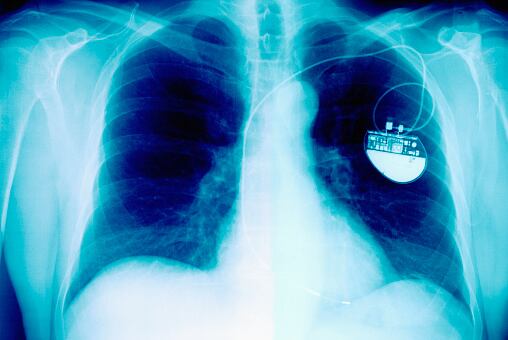

Actualmente, millones de personas en todo el mundo utilizan marcapasos que generan impulsos eléctricos para regular el ritmo cardíaco.

Actualmente los marcapasos temporales requieren una intervención quirúrgica para coser electrodos a los músculos cardíacos, cuyos cables están conectados a un aparato colocado en el pecho del paciente.

Cuando el marcapasos deja de ser necesario, los médicos retiran los cables, lo que puede provocar daños.